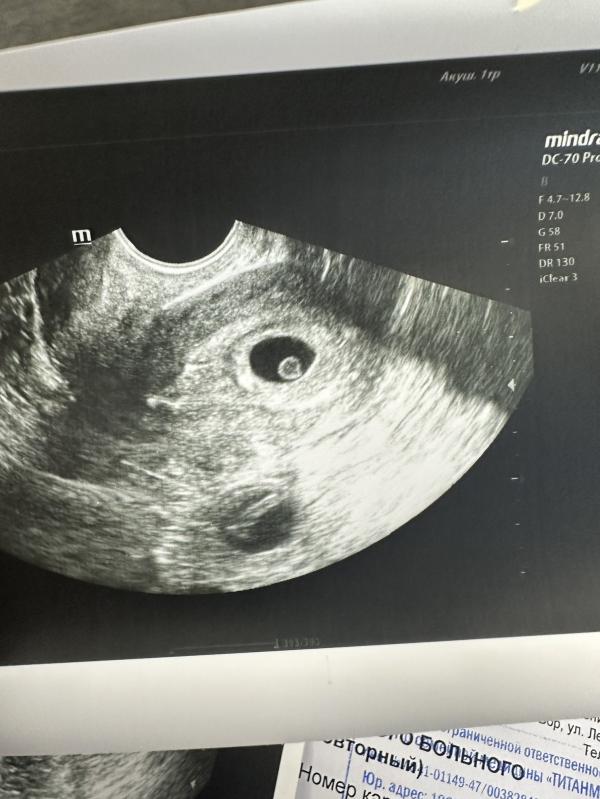

Девчулииии, доброе утро ☀️ все услышали, увидели❤️Даже сердечко дали послушать🙏🏻🫶🏻Из за поздней овуляции сроки скачут, но врач сказала потом догоним ✨

Ну вот у меня сегодня по месячным 7 недель и все услышали ✨🫶🏻Попробуйте тоже в 7 сходить)

Поздравляю, прям как у меня , 6 недель, КТР 0,34 )))